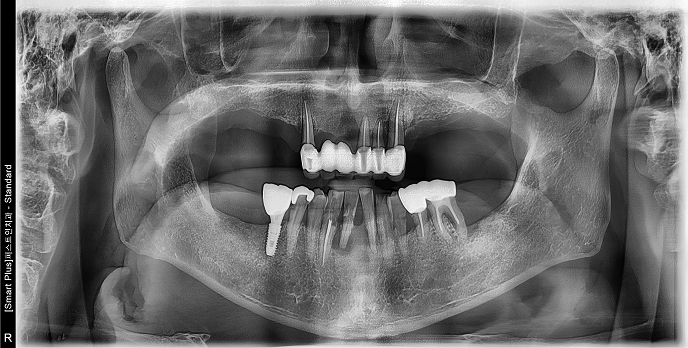

• 70대 남성 | 치주염 | 임플란트 | 치료기간 4개월

Before 2024.12.06

After 2025.04.11